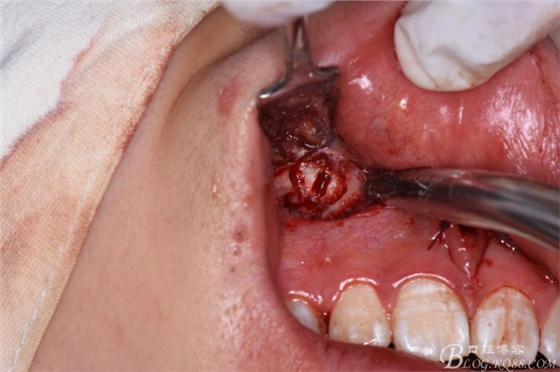

圖20. 在12、13根尖所對應(yīng)的前廳溝處做第二個弧形切口

圖21.一定要切透粘骨膜。

圖22.翻瓣、暴露骨面